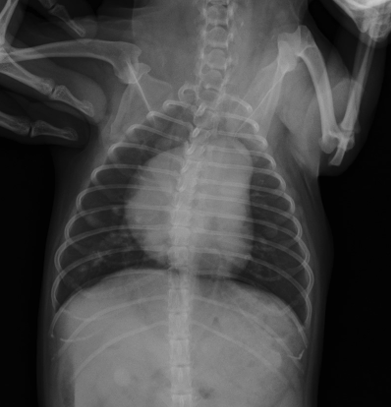

Interstitial pattern

aorta and vena cava is blurry

DV